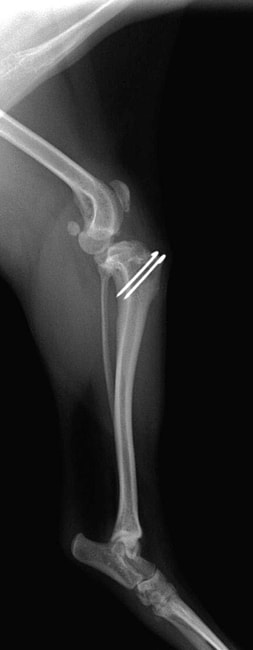

■ 症例20 ポメラニアン 8ヶ月 1.8kg

左右膝蓋骨脱臼 グレードⅢ

2ヶ月前から間欠的跛行が認められ、両膝の膝蓋骨脱臼整復術を行った。

手技は縫工筋及び内側広筋の解放、脛骨粗面の外側転位、滑車ブロック形造溝術、内外側関節包の縫縮を選択し実施した。

右側の膝蓋骨脱臼は上記手技で整復されたものの、左側はそれのみでは膝蓋骨が浮く様子が認められた。その為、PDS縫合糸にて膝蓋靱帯を1糸のみ縫合し、靱帯の縫縮を行った。

膝蓋骨脱臼は膝関節における膝蓋骨の内外側の脱臼と定義されるが、時として単純な内外の脱臼ではなく、膝蓋骨が大きく前方に浮き上がるように脱臼する場合がある。特にトイプードルやポメラニアンといった犬種に多く認められる。

内側脱臼に加えて前方への浮き上がりを矯正する為に、従来より脛骨粗面転移により膝蓋靭帯を外方と下方に引っ張り、固定する方法を選択する。膝蓋骨の前方への浮き上がりが軽度の場合は、従来法ではなく関節包の縫縮で対応していた。しかし、一部の症例で膝蓋骨の動きが悪くなり伸展機構が円滑に機能せずロボット様歩行になるケースがあった。

その為、膝蓋靭帯自体を縫縮する方法を採用した。この方法により、膝関節の伸展機構を妨げず膝蓋骨の軽度の浮きを矯正することが可能となった。

本症例の経過は良好である